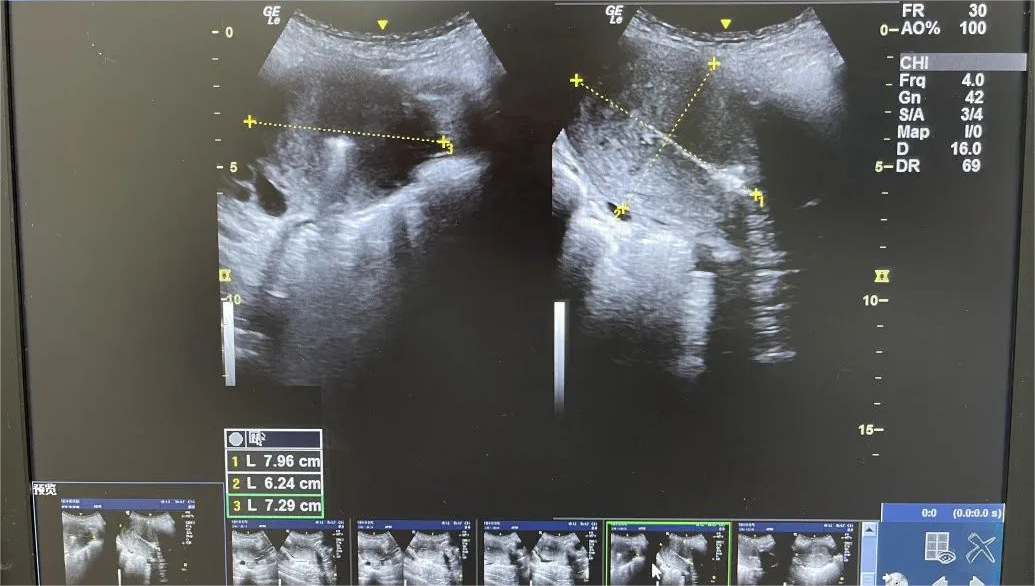

2、准确定位

手术过程由可视超声技术引导、监控,在显示屏幕上即可直接观察宫腔内部状况。可视状态让手术更安全,避免了不当操作。

传统的人工流产,无法窥视宫腔状况。在超声引导下做手术,在屏幕上即可直接观察宫腔内部状况,确定孕囊方位,对绒毛进行定点吸引。医生看着屏幕做手术,准确性得到大幅度提高。